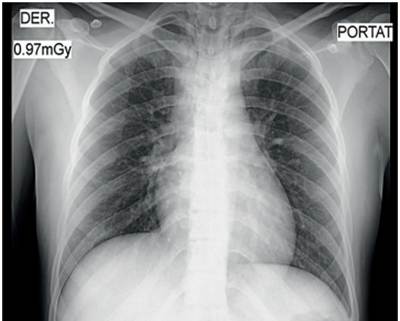

Ante la sospecha clínica de lesión vascular cervical como primera posibilidad, se tomó una radiografía de tórax postero-lateral que descartó la presencia de neumotórax, hemotórax u otra complicación (figura 3). Se realizó un angiotac cervical con contraste endovenoso, encontrando enfisema subcutáneo en los tejidos blandos, con solución de continuidad (figura 4) y una lesión en el tercio medio de la tráquea, con compromiso de su pared lateral derecha (figura 5), sin poder descartar una lesión del esófago en su segmento cervical. No se observó compromiso vascular ni óseo.